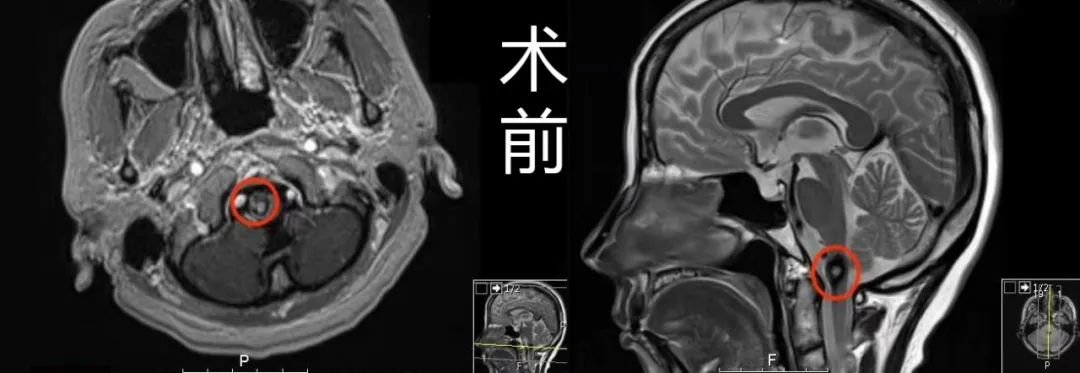

术前MR:延颈髓偏右侧见一直径约1cm占位,周围见环状含铁血黄素低信号影环绕,提示海绵状血管瘤。

(术前术后MR对比)